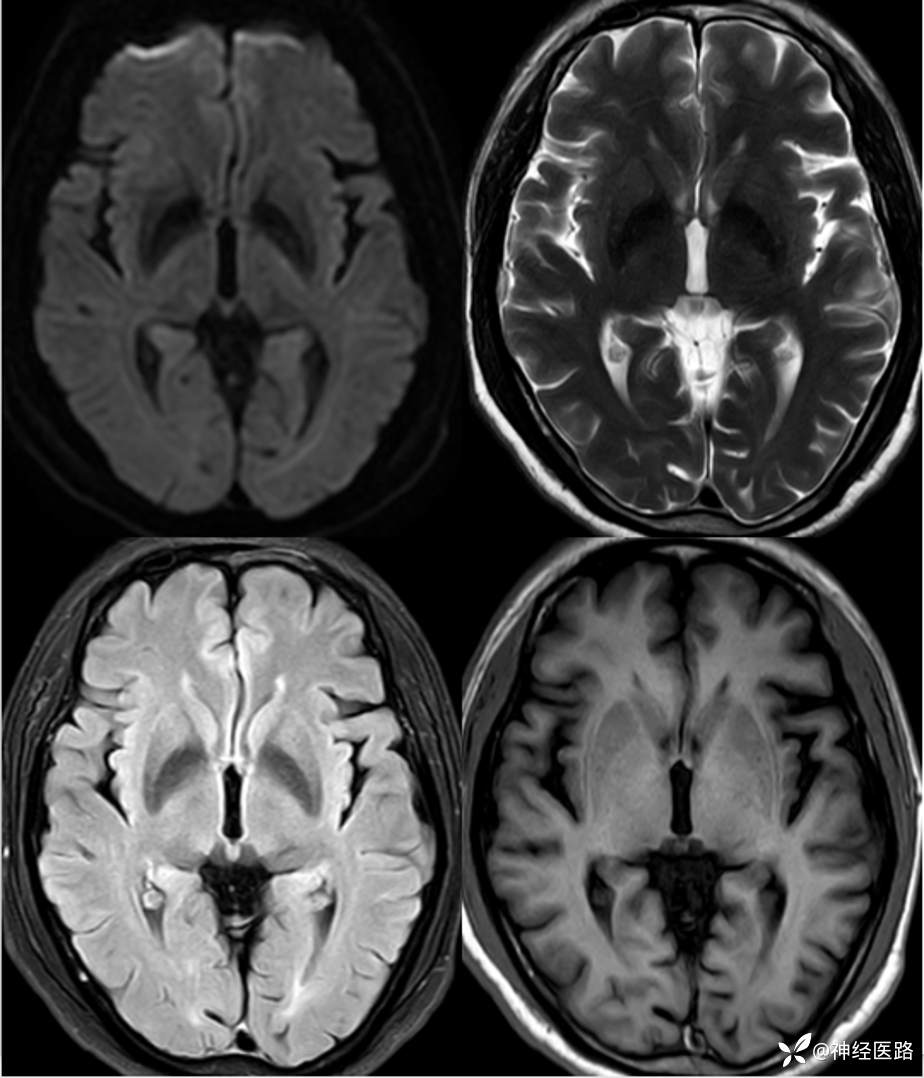

辅助检查:头部磁共振:1.颅脑DWI未见明显异常扩散受限。 2.脑白质高信号,脑萎缩。3.双侧上颌窦、双侧筛窦、双侧额窦炎。

补充1年余前直立倾斜试验、肌电图及头部磁共振检查资料。

两次影像对比